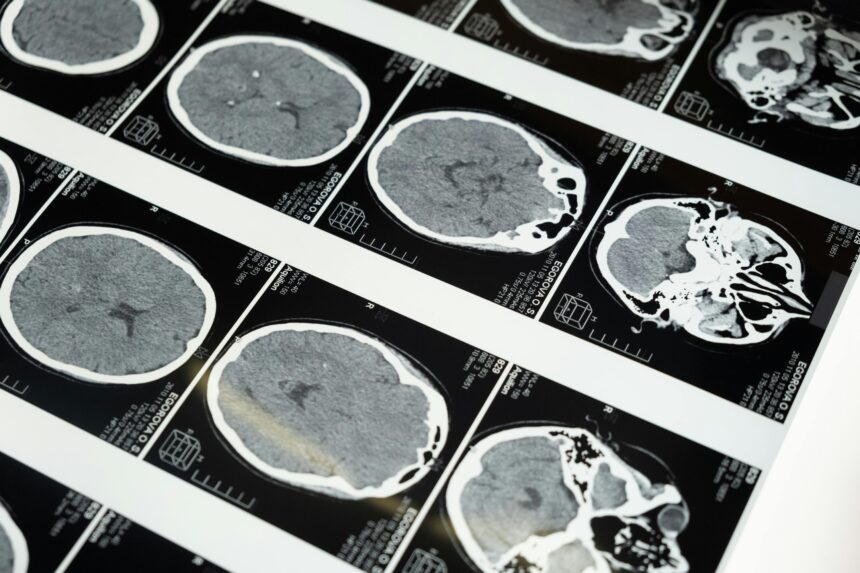

Essas doenças afetam o cérebro. A mais conhecida nos humanos é a doença de Creutzfeldt-Jakob (DCJ). Ela causa perda de memória, alterações de comportamento e de movimentos. A progressão é acelerada e leva ao óbito.

Doenças priônicas afetam o cérebro. São raras, mas perigosas.

Com o tempo, esses “blocos” mal dobrados se juntam e formam agregados. Eles são rígidos, parecidos com fibras. No tecido, vemos lesões microscópicas que lembram uma esponja. O resultado é perda de neurônios e de funções cerebrais.